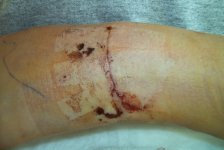

Tim's Shortarm The Ulnar Shortening Scar

Scar

Scar Splint

Fusion Scar @6 Weeks Post-op